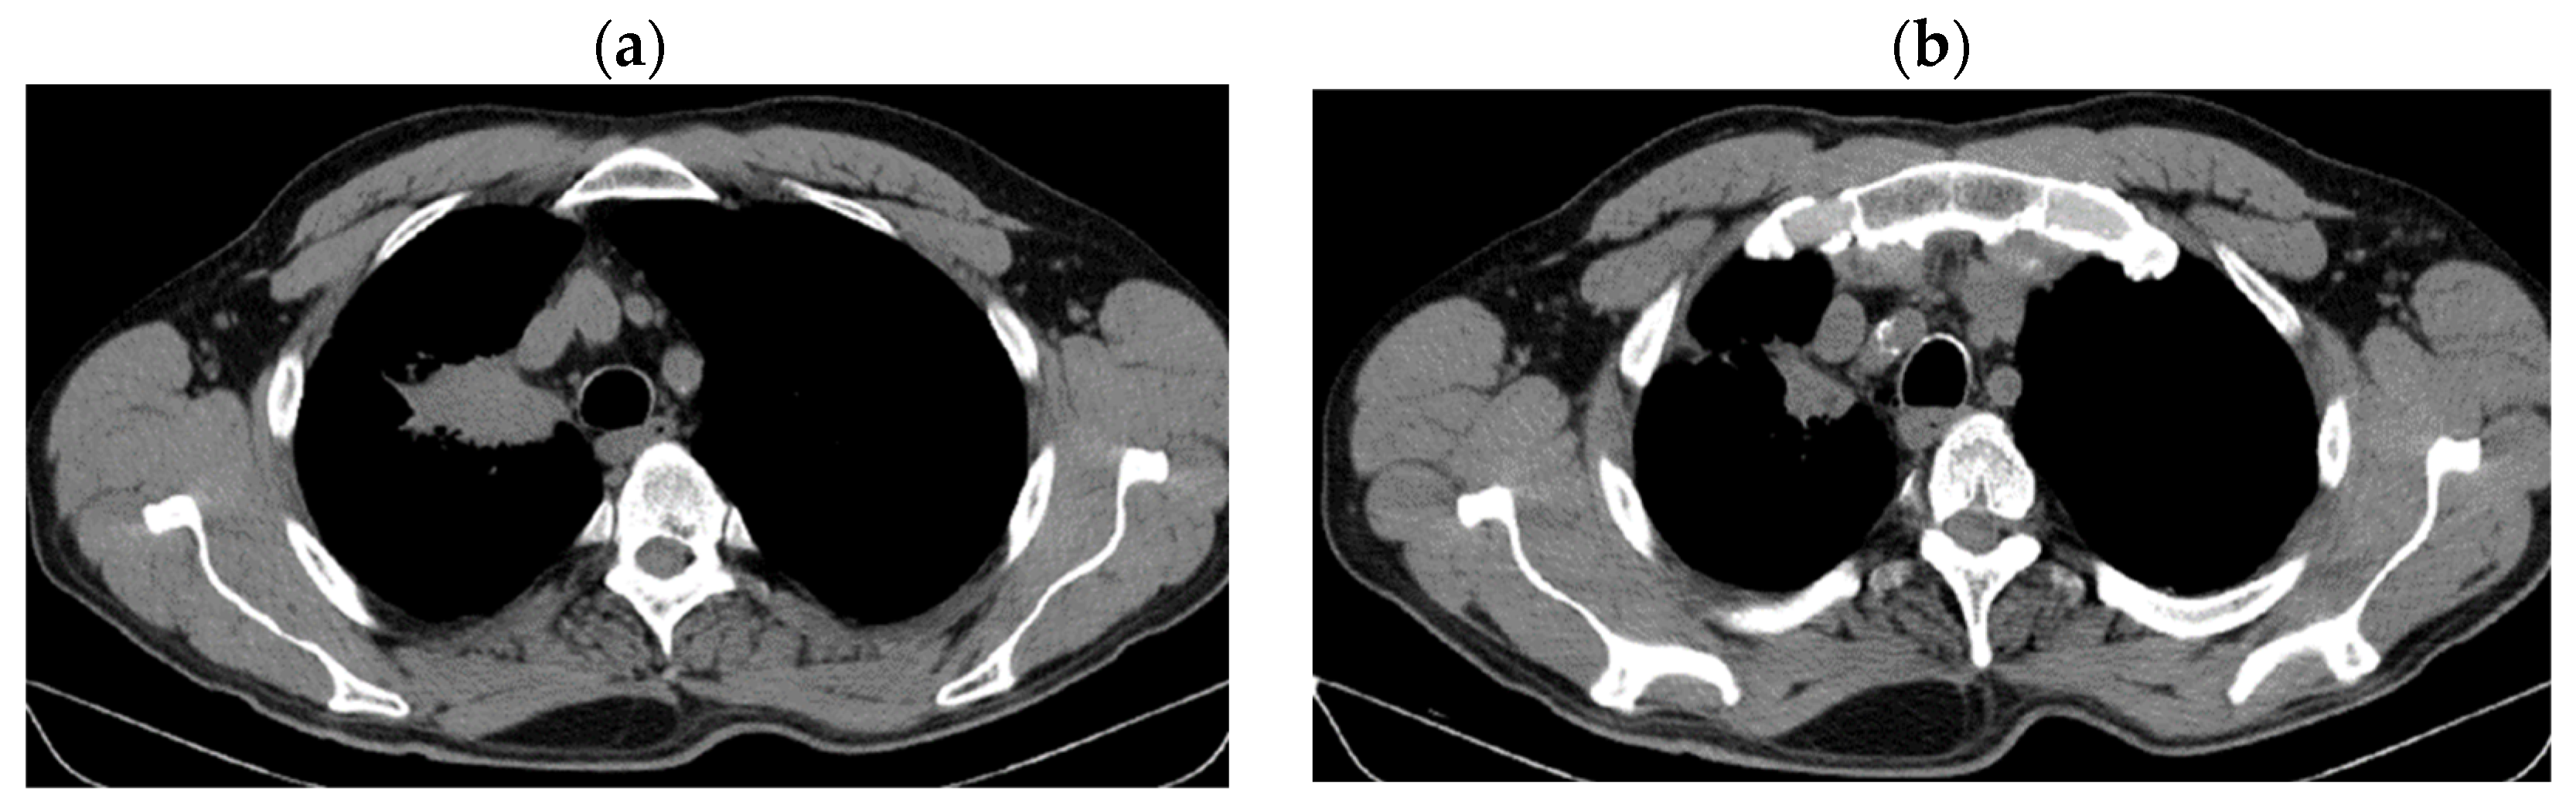

2. Case Presentation

2.2. Monitoring 2022: Oncological Commission 1910/16.08.2022

2.3. Oncological Committee 07/25/2023 Recommended